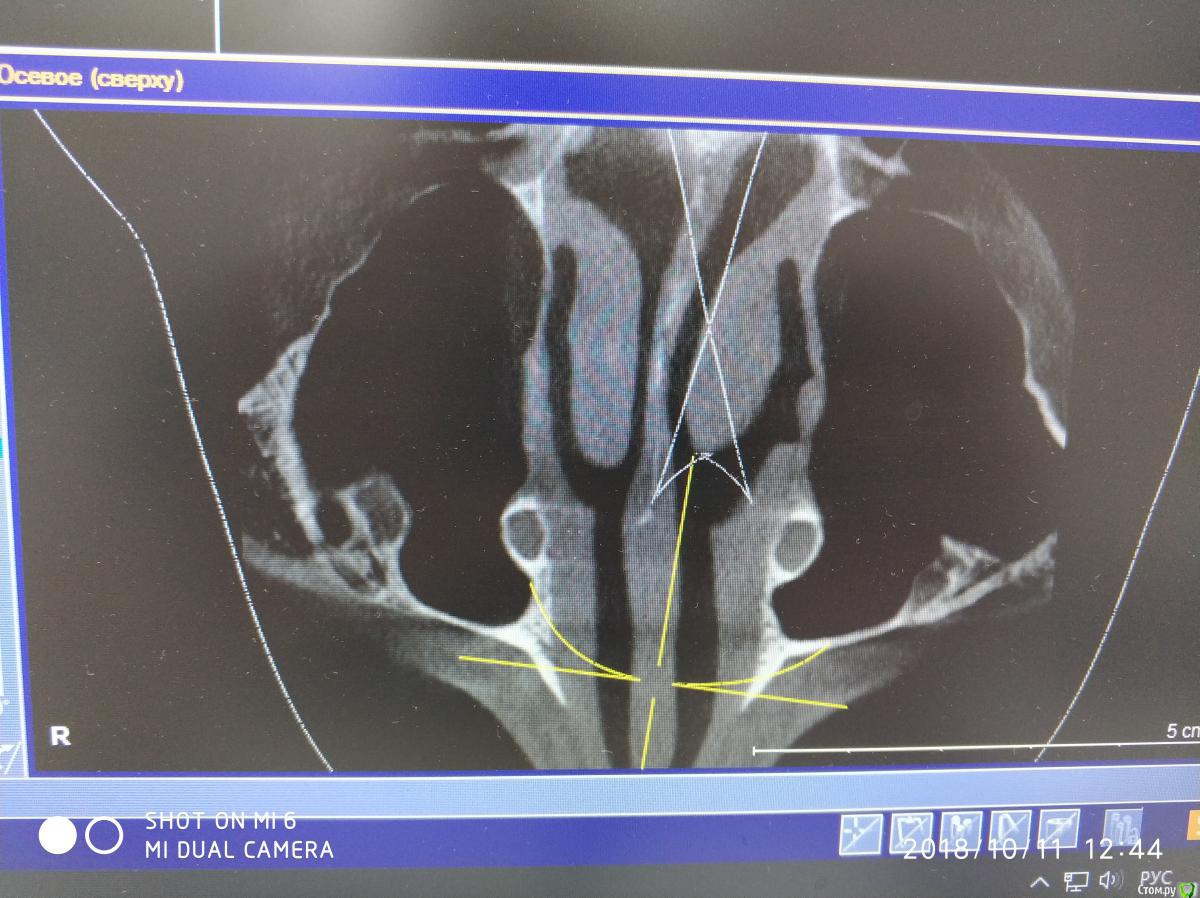

Nazim_NV86 Опубликовано 11 октября, 2018 Автор Поделиться Опубликовано 11 октября, 2018 (изменено) Женщина. Примерно 50-53. Скрины синуса сделал, но замотался и забыл выложить. Синусы вч оба чистые. Слева правда есть маленькое мукоцеле. Сегодня предложил ей снять коронки и походить с формирователями. По семейным причинам уехала к дочери помогать. Отложили на месяц. Так у нас есть месяц на расследование ) Изменено 11 октября, 2018 пользователем Nazim_NV86 Ссылка на комментарий

Nazim_NV86 Опубликовано 12 октября, 2018 Автор Поделиться Опубликовано 12 октября, 2018 Срезы пазух. На чувствительность языка жалоб не слышал. Как приедет тесты сделаю. Ссылка на комментарий

Nazim_NV86 Опубликовано 2 февраля, 2019 Автор Поделиться Опубликовано 2 февраля, 2019 (изменено) В продолжении беседы:02.08.16г. была микрогайморотомия справа ( ДЗ выписке: киста г.п.).10.08.17г. поставлены 14,16 с открытым синус-лифтингом(апатос микс+эволюшн). Синус был чистый как до, так и после операции. Соустье работало.18.01.18г. поставлены 45,46. После операций никаких особенностей. 19.04.18г. 4 фдм. И примерно в это время (со слов) появились проблемы с запахами. Коронки сданы 29.05.18г.При допросе (настойчивом) оказалось что пациентка часто болеет ОРЗ и постоянно лечится. Аллергоанамнез оказался впечатляющий. В анкете об этом нет информации. Перечень всего на что у неё была аллергия большой. Попросил перечислить мне на бумаге.На контр осмотр не пришла, поскольку снова заболела. Иммуноглобулины: А - 0,39 (0,65-4,21); М - 0,72 (0,33-2,93); G - 18,64 (5,52-16,31). от 23.01.19г Попросил сдать сам.Заключение МРТ от 21.08.18г. МР-картина очагов глиоза в белом веществе головного мозга сосудистого характера, умеренной наружной заместительной гидроцефалии. Данных за объёмные патологические образования и ишемические изменения не получено. Жду результатов других анализов (направлял терапевт). Изменено 2 февраля, 2019 пользователем Nazim_NV86 1 Ссылка на комментарий